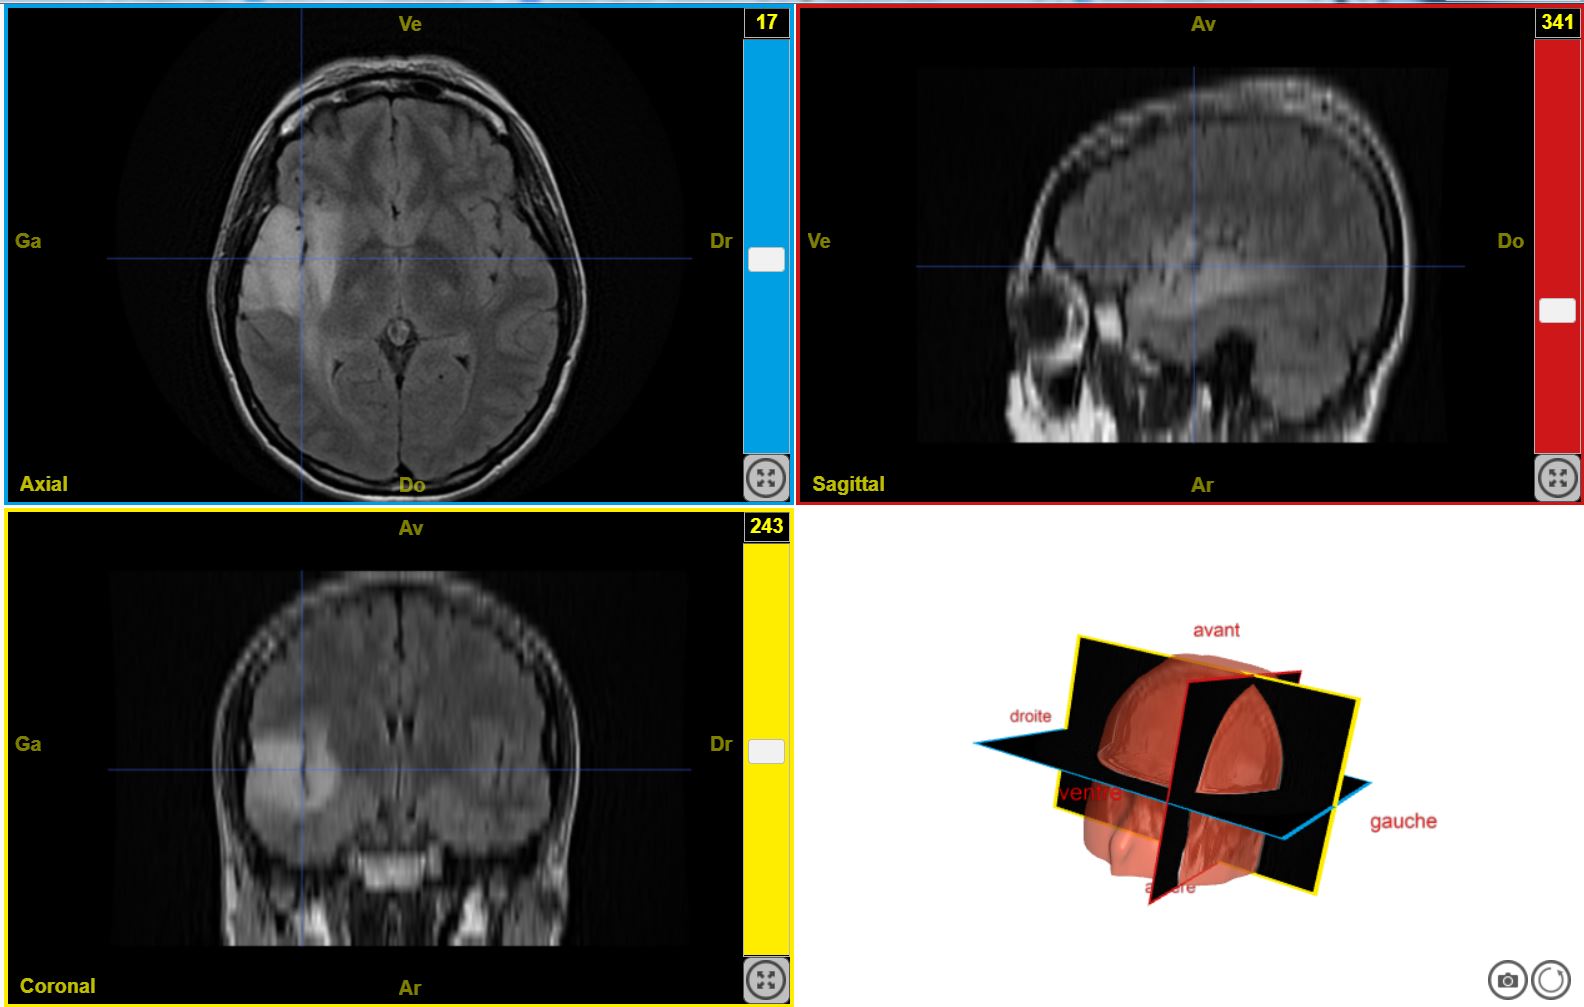

TumeurHallucinationAuditiveT2Flair